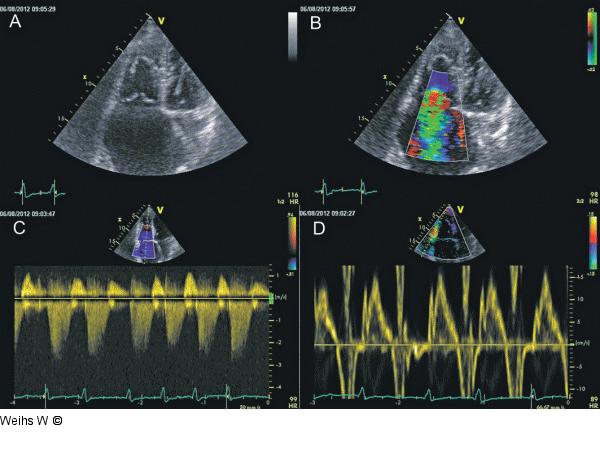

Abbildung 1: Trikuspidalinsuffizienz Hochgradige Trikuspidalinsuffizienz in der herkömmlichen Echokardiographie. Hochgradige Dilatation des rechten Ventrikels und Vorhofs mit Koaptationsdefekt der Trikuspidalklappe (A), hochgradige Trikuspidalinsuffizienz im Farbdoppler (B) und CW-Doppler (C). Tissuedoppler des Trikuspidalanulus (D). |

Hochgradige Trikuspidalinsuffizienz in der herkömmlichen Echokardiographie. Hochgradige Dilatation des rechten Ventrikels und Vorhofs mit Koaptationsdefekt der Trikuspidalklappe (A), hochgradige Trikuspidalinsuffizienz im Farbdoppler (B) und CW-Doppler (C). Tissuedoppler des Trikuspidalanulus (D). |